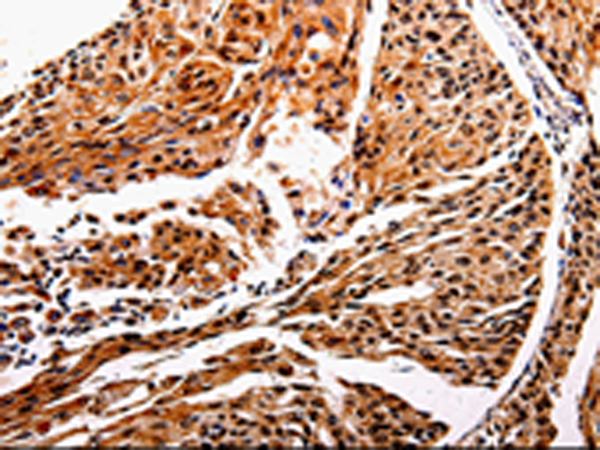

ELISA, IHC |

IHC positive control: |

Human cervical cancer and human esophagus cancer |

IHC Recommend dilution: |

25-100 |